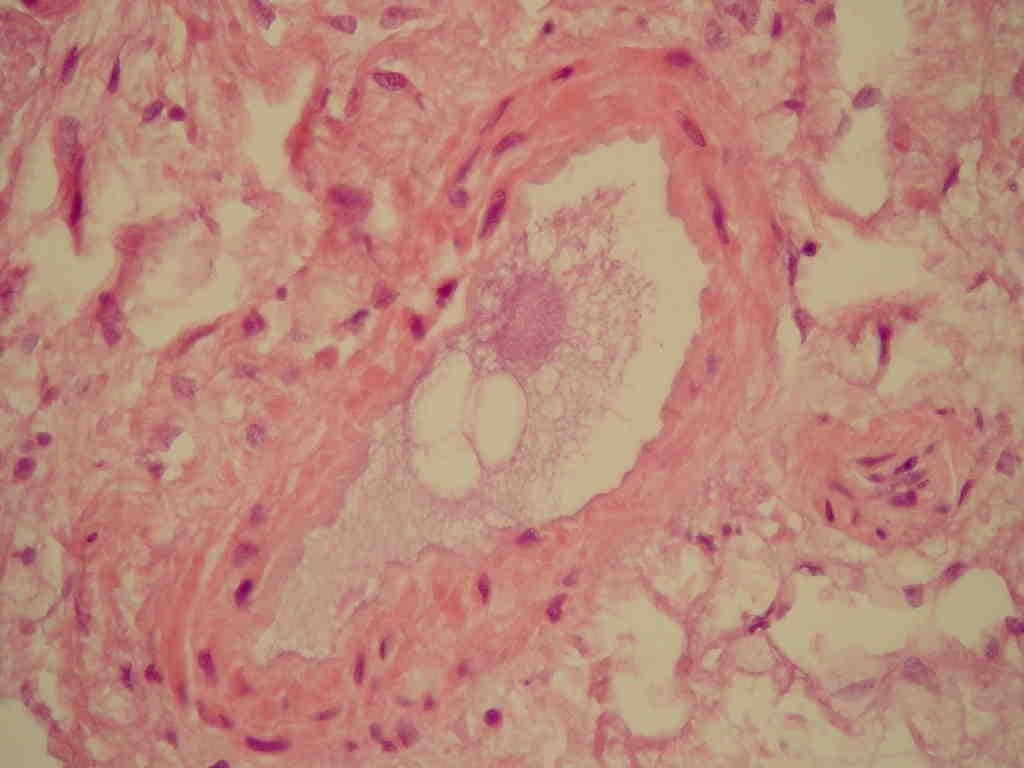

Fat embolism syndrome occurs when fat enters the blood stream (fat embolism) and results in symptoms. Symptoms generally begin within a day. This may include a petechial rash, decreased level of consciousness, and shortness of breath. Other symptoms may include fever and decreased urine output. The risk of death is about 10%. Fat embolism most commonly occurs as a result of fractures of bones such as the femur or pelvis. Other potential causes include pancreatitis, orthopedic surgery, bone marrow transplant, and liposuction. The underlying mechanism involves widespread inflammation. Diagnosis is based on symptoms. Treatment is mostly supportive care. This may involve oxygen therapy, intravenous fluids, albumin, and mechanical ventilation. While small amounts of fat commonly occur in the blood after a bone fracture, fat embolism syndrome is rare. The condition was first diagnosed in 1862 by Zenker. Symptoms of fat embolism syndrome (FES) can start from 12 hours to 3 days after diagnosis of the underlying clinical disease. The three most characteristic features are: respiratory distress, neurological features, and skin petechiae. Respiratory distress (present in 75% of the cases) can vary from mild distress which requires supplemental oxygen to severe distress which requires mechanical ventilation. For neurologic features, those who have FES may become lethargic, restless, with a drop in Glasgow Coma Scale (GCS) due to cerebral oedema rather than cerebral ischaemia. Therefore, neurological signs are not lateralised to one side of the body. In the severe form of cerebral edema, a person may become unresponsive. Petechiae rash usually happens in 50% of the patients. Such skin manifestation is temporary and can disappear within one day. The fat embolism syndrome can be divided into three types: Subclinical FES - It manifests as reduced partial pressure of oxygen (PaO2) on arterial blood gas (ABG) with deranged blood parameters (reduced haemoglobin or thrombocytopenia) associated with fever, pain, discomfort, tachypnoea, tachycardia.